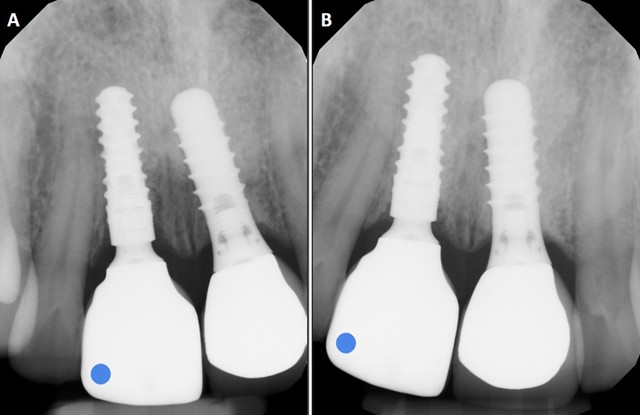

Radiographs, by contrast, give clear and reproducible insight into implant osseointegration and crestal bone stability.7 In the same patient, periapical films from 2021 and 2025 (Figure 2) confirm stable bone levels at #11. However, while radiographs reassure the clinician that the fixture is integrated, they are blind to surface tissue contours that determine long-term esthetics.7 Patients do not typically notice crestal bone levels; they perceive small shifts in visible tissues such as the mucosal margin or contour. These esthetic changes often begin subtly and may go unnoticed at first, only becoming evident after years of gradual progression.3 Conventional records, whether photographic or radiographic, provide little help in identifying these early stages.6,7

Fig. 2